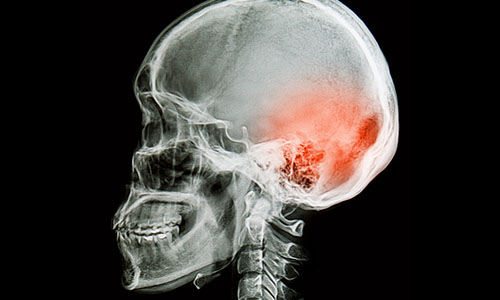

Avec les sports de contact et la venue des sports extrêmes, on entend de plus en plus parler de Commotion Cérébrale. Toutefois, elle peut affecter toute personne qui subit un accident quelconque. La commotion cérébrale est un traumatisme crânien léger reçu par le cerveau lors d’un choc direct ou indirect à la tête. Elle se manifeste par une perte temporaire et totalement réversible des fonctions neurologiques du cerveau. Les causes de cette affectation sont de toutes évidences les divers accidents subits tels : les accidents de la route, de travail ou lors de pratique sportive pour ne nommer que ceux-ci.

Malgré l’appellation « traumatisme crânien léger » et l’aspect bénin que peut parfois référer la commotion cérébrale, il est toutefois important ne pas négliger sa surveillance. Effectivement, dans ce type d’affectation le cerveau est soumis à des forces biomécaniques traumatiques de vas et viens à l’intérieur de la boite crânienne pouvant causer des dommages à la masse cérébrale. Ainsi, la surveillance des signes et symptômes associés à la commotion cérébrale nous informent sur la gravité ou non des fonctions atteintes.